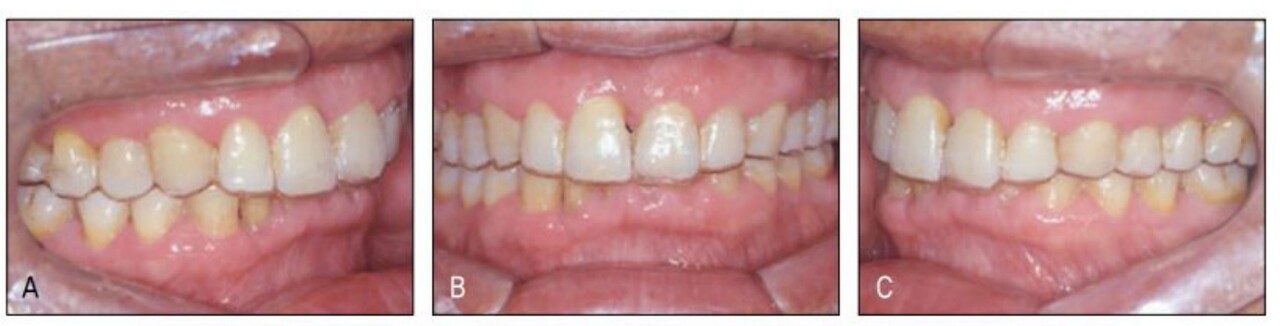

그러나 전치부 과개교합으로 상악설측면에서의 장치 부착이 불가하여 환자에게 투명교정장치를 설명하였고 이 역시 심미적 장치이어 환자가 수락하고 투명교정장치로 간단하게 공간클로져 교정을 시행 하였다. 가철식 장치이어서 다소의 경사이동이 발생하였고 치주질 환으로 우측의 중절치가 더 정출하여 비심미적인 절단연이었으나 스트리핑 그리고 re-shaping 등을 이용하여 심미적인 절단연을 만들어주었다. 교정을 주저하였던 환자는 설측및 투명장치 등 심미적 장치로 인해 교정치료 내내 크게 만족해 하였다(그림 23-7~10).